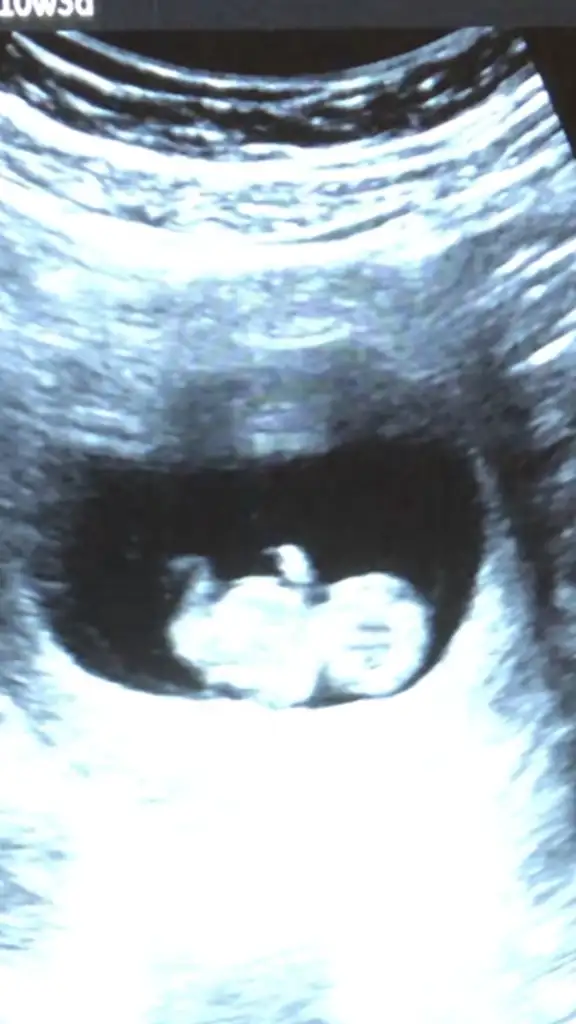

Bana da bakar mısınız 9+3

16.11.1996 doğum tarihi sat 30 Mart ama geç döllenme olduğu için doktor nişanı haz alıyor hafta da ona göre gidiyor

• IMG_20230616_120442.webp

IMG_20230616_120442.webp

19,1 KB · Görüntüleme: 86